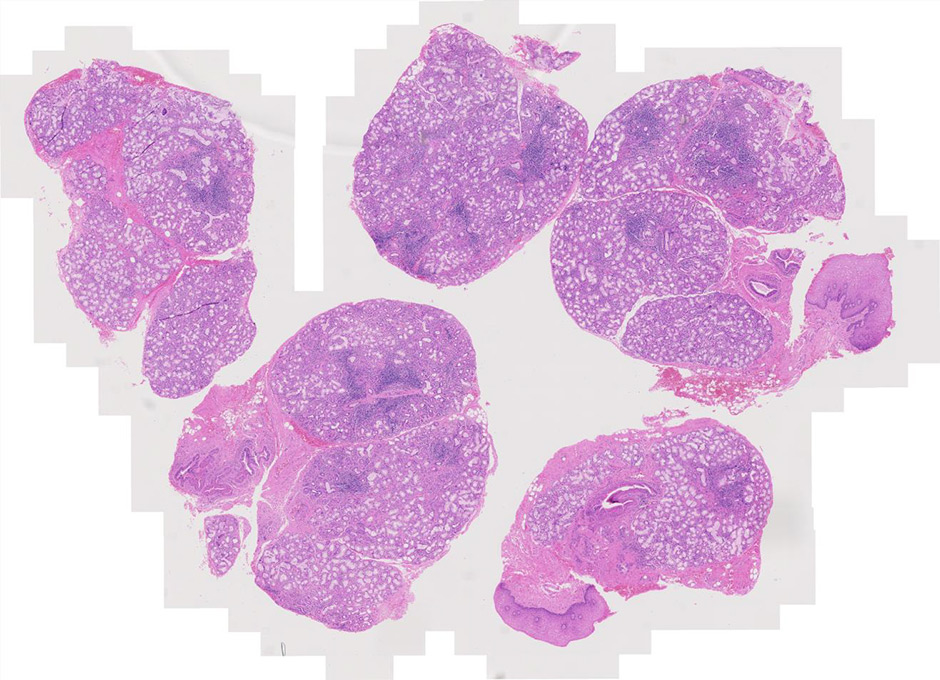

Figure 1

Haematoxylin and eosin staining of salivary gland biopsy section showing several periepithelial mononuclear cell infiltrates, i.e. focal lymphocytic sialoadenitis.

Histologically, pSS is characterised by the formation of periepithelial mononuclear cell infiltrates (fig. 1). The aggregates preferentially form in the exocrine glands: salivary glands, lachrymal glands and exocrine pancreas. The histological lesions typical of SS occur in both major and minor salivary glands. Although the major salivary glands, in particular parotid glands, are often the sites of formation for the B cell lymphoma, in the majority of cases, it is not justifiable to obtain a major salivary gland biopsy owing to its inconvenience to patients and the possible complication of salivary fistula, scarring and facial nerve damage [13]. Few groups with a specific interest in SS routinely perform major salivary gland biopsy, which, however, in experienced hands, has a rather acceptable safety profile. Nonetheless, minor salivary gland biopsy can be obtained in a day-care facility with minimal invasiveness and discomfort [14]. Studies looking at the concordance of the histological lesions between the major and minor glands are reassuring, showing similar diagnostic sensitivity and specificity [15]. Nonetheless, the predominance of lymphoepithelial lesions (areas of lymphocytic infiltration of the duct that result in atrophy of the columnar ductal epithelium and proliferation of the basal epithelial cells [fig. 2]) and the detection of better-organised germinal centres in the former in the major but not minor salivary glands has to be acknowledged [16–18].